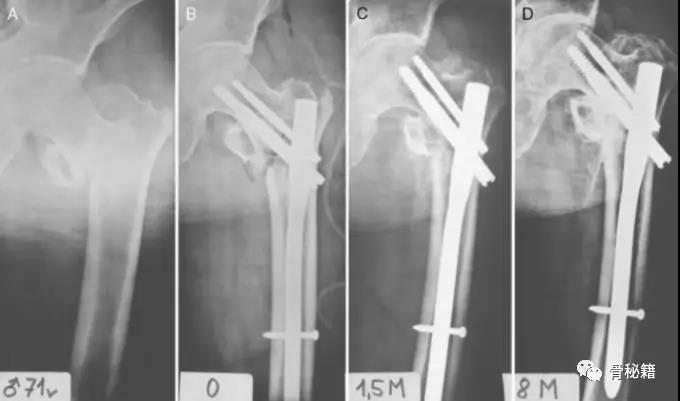

一个双膦酸盐治疗5年的患者粗隆下非典型骨折

采用了髓内钉固定,术后一年内固定失效

更换了DCS+植骨固定,术后四个月又发现了内固定失效再次更换了更长的DCS

这次的固定能成功吗?